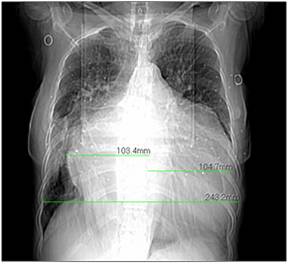

胸片提示:双肺纹理增强模糊,左侧少量胸腔积液,心胸比0.81。